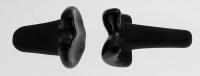

Pyrolytic carbon implants for proximal interphalangeal joints (above) and metacarpophalangeal joints (below).  Another proximal interphalangeal joint post traumatic reconstruction is shown here and an example of metacarpophalangeal joint implants is posted here.

Middle phalanx base component on the left, proximal phalanx base component on the right, palmar articular views.

lateral view.

Palmar view.

Dorsal view.